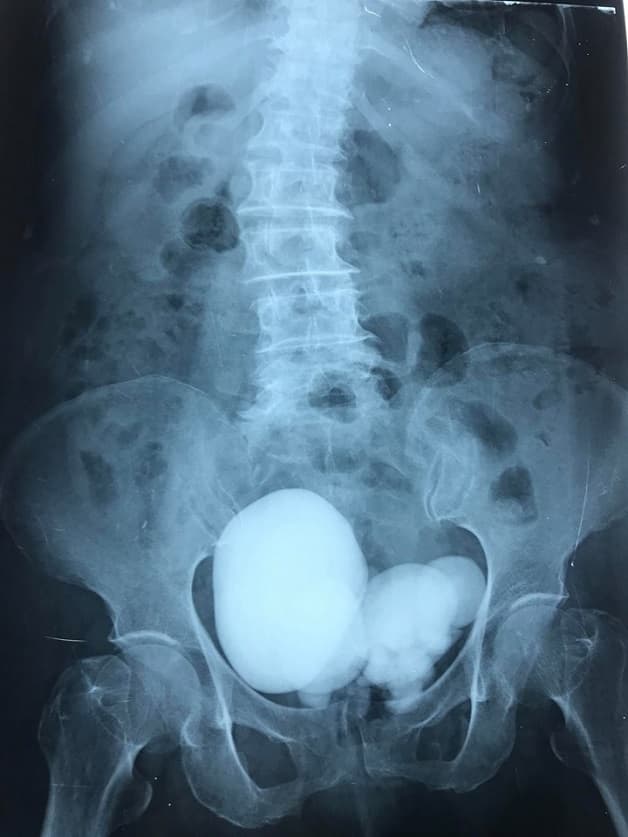

– Chụp X-quang thận – Niệu quản – Bàng quang: Phương pháp này giúp xác định sỏi. Tuy nhiên có một số loại sỏi không cản quang thì không thể nhìn được qua chụp X-quang thông thường.

Chụp X- quang giúp quan sát tình trạng sỏi